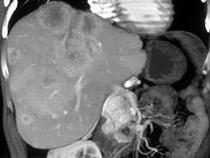

男,48岁,胃癌术后1年,未化疗,CT检查如图所示,最可能诊断为()A.肝癌B.肝转移癌C.肝血管瘤D.肝脓肿E.肝囊肿

问题 男,48岁,胃癌术后1年,未化疗,CT检查如图所示,最可能诊断为()

选项 A.肝癌 B.肝转移癌 C.肝血管瘤 D.肝脓肿 E.肝囊肿

答案 B